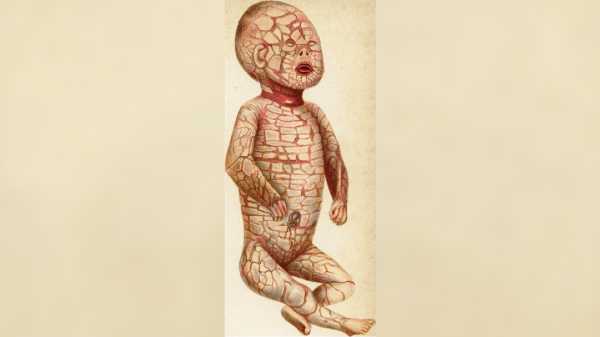

Рідкісне генетичне захворювання, яке призводить до появи твердої «луски» у немовлят

Рідкісне генетичне захворювання, яке призводить до появи твердої «луски» у немовлят